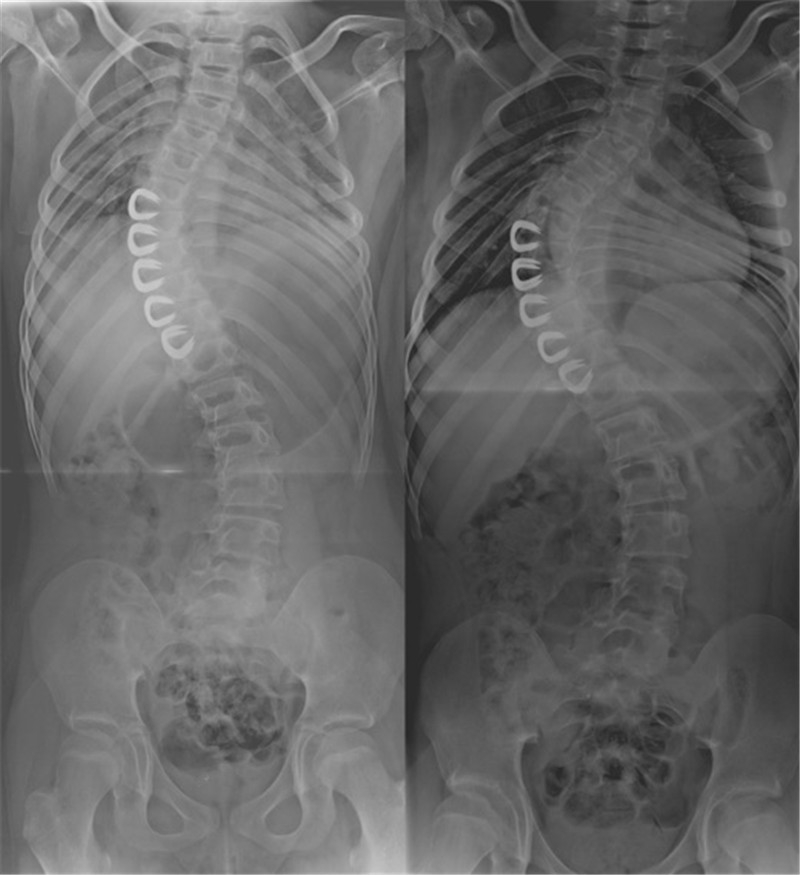

纵向可延伸式钛肋假体技术(vertical expandable prosthetic titanium rib,VEPTR)最初用于胸廓发育不良综合症(TIS),EOS患者因肋畸形而部分伴有胸廓发育不全。该技术利用凹侧钛合金肋骨撑开器扩张肋骨和胸廓,促进肋骨的生长发育,从而间接矫正脊柱畸形(图 4)。

VEPTR无需长节段剥离,故而避免了脊柱自发融合。因此,VEPTR在部分矫正畸形并保留了脊柱纵向生长能力的同时,扩大了胸腔,可明显改善患儿肺功能。

2009年,Hasler等[5]对比生长棒和VEPTR的矫形效果,显示VEPTR在冠状面的矫形效果不及生长棒,然而其控制矢状面和骨盆倾斜的效果较之生长棒更好。

2017年,Gantner等[6]回顾性分析了32例VEPTR患者,随访2.6-3.6年,结果显示对于EOS患儿,VEPTR可以较好地代替生长棒达到治疗效果,但其长期随访显示矫形效果下降。VEPTR的主要并发症为无症状型近端内固定移位。